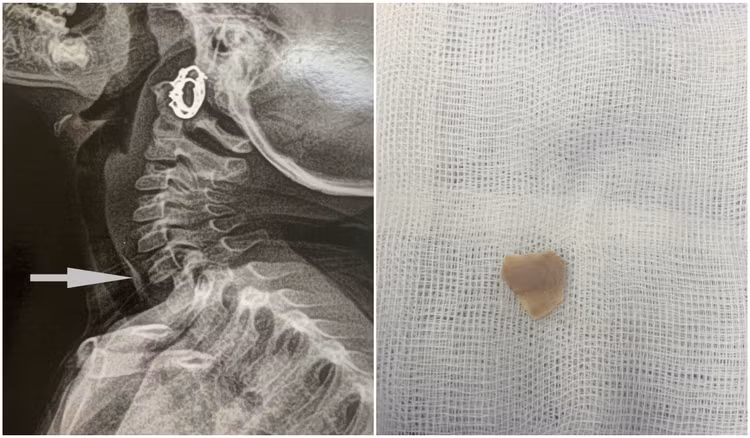

| Hình ảnh bệnh nhi 3 tuổi bị hóc xương vùng thực quản cổ - Ảnh BVCC |

Trường hợp thứ 3 là bệnh nhi Vũ Hà A. (3 tuổi), nhập viện ngày 8/2/2025 do bị hóc xương gà vùng thực quản cổ. Các bác sĩ khoa Tai mũi họng nội soi lấy dị vật an toàn cho bệnh nhi.